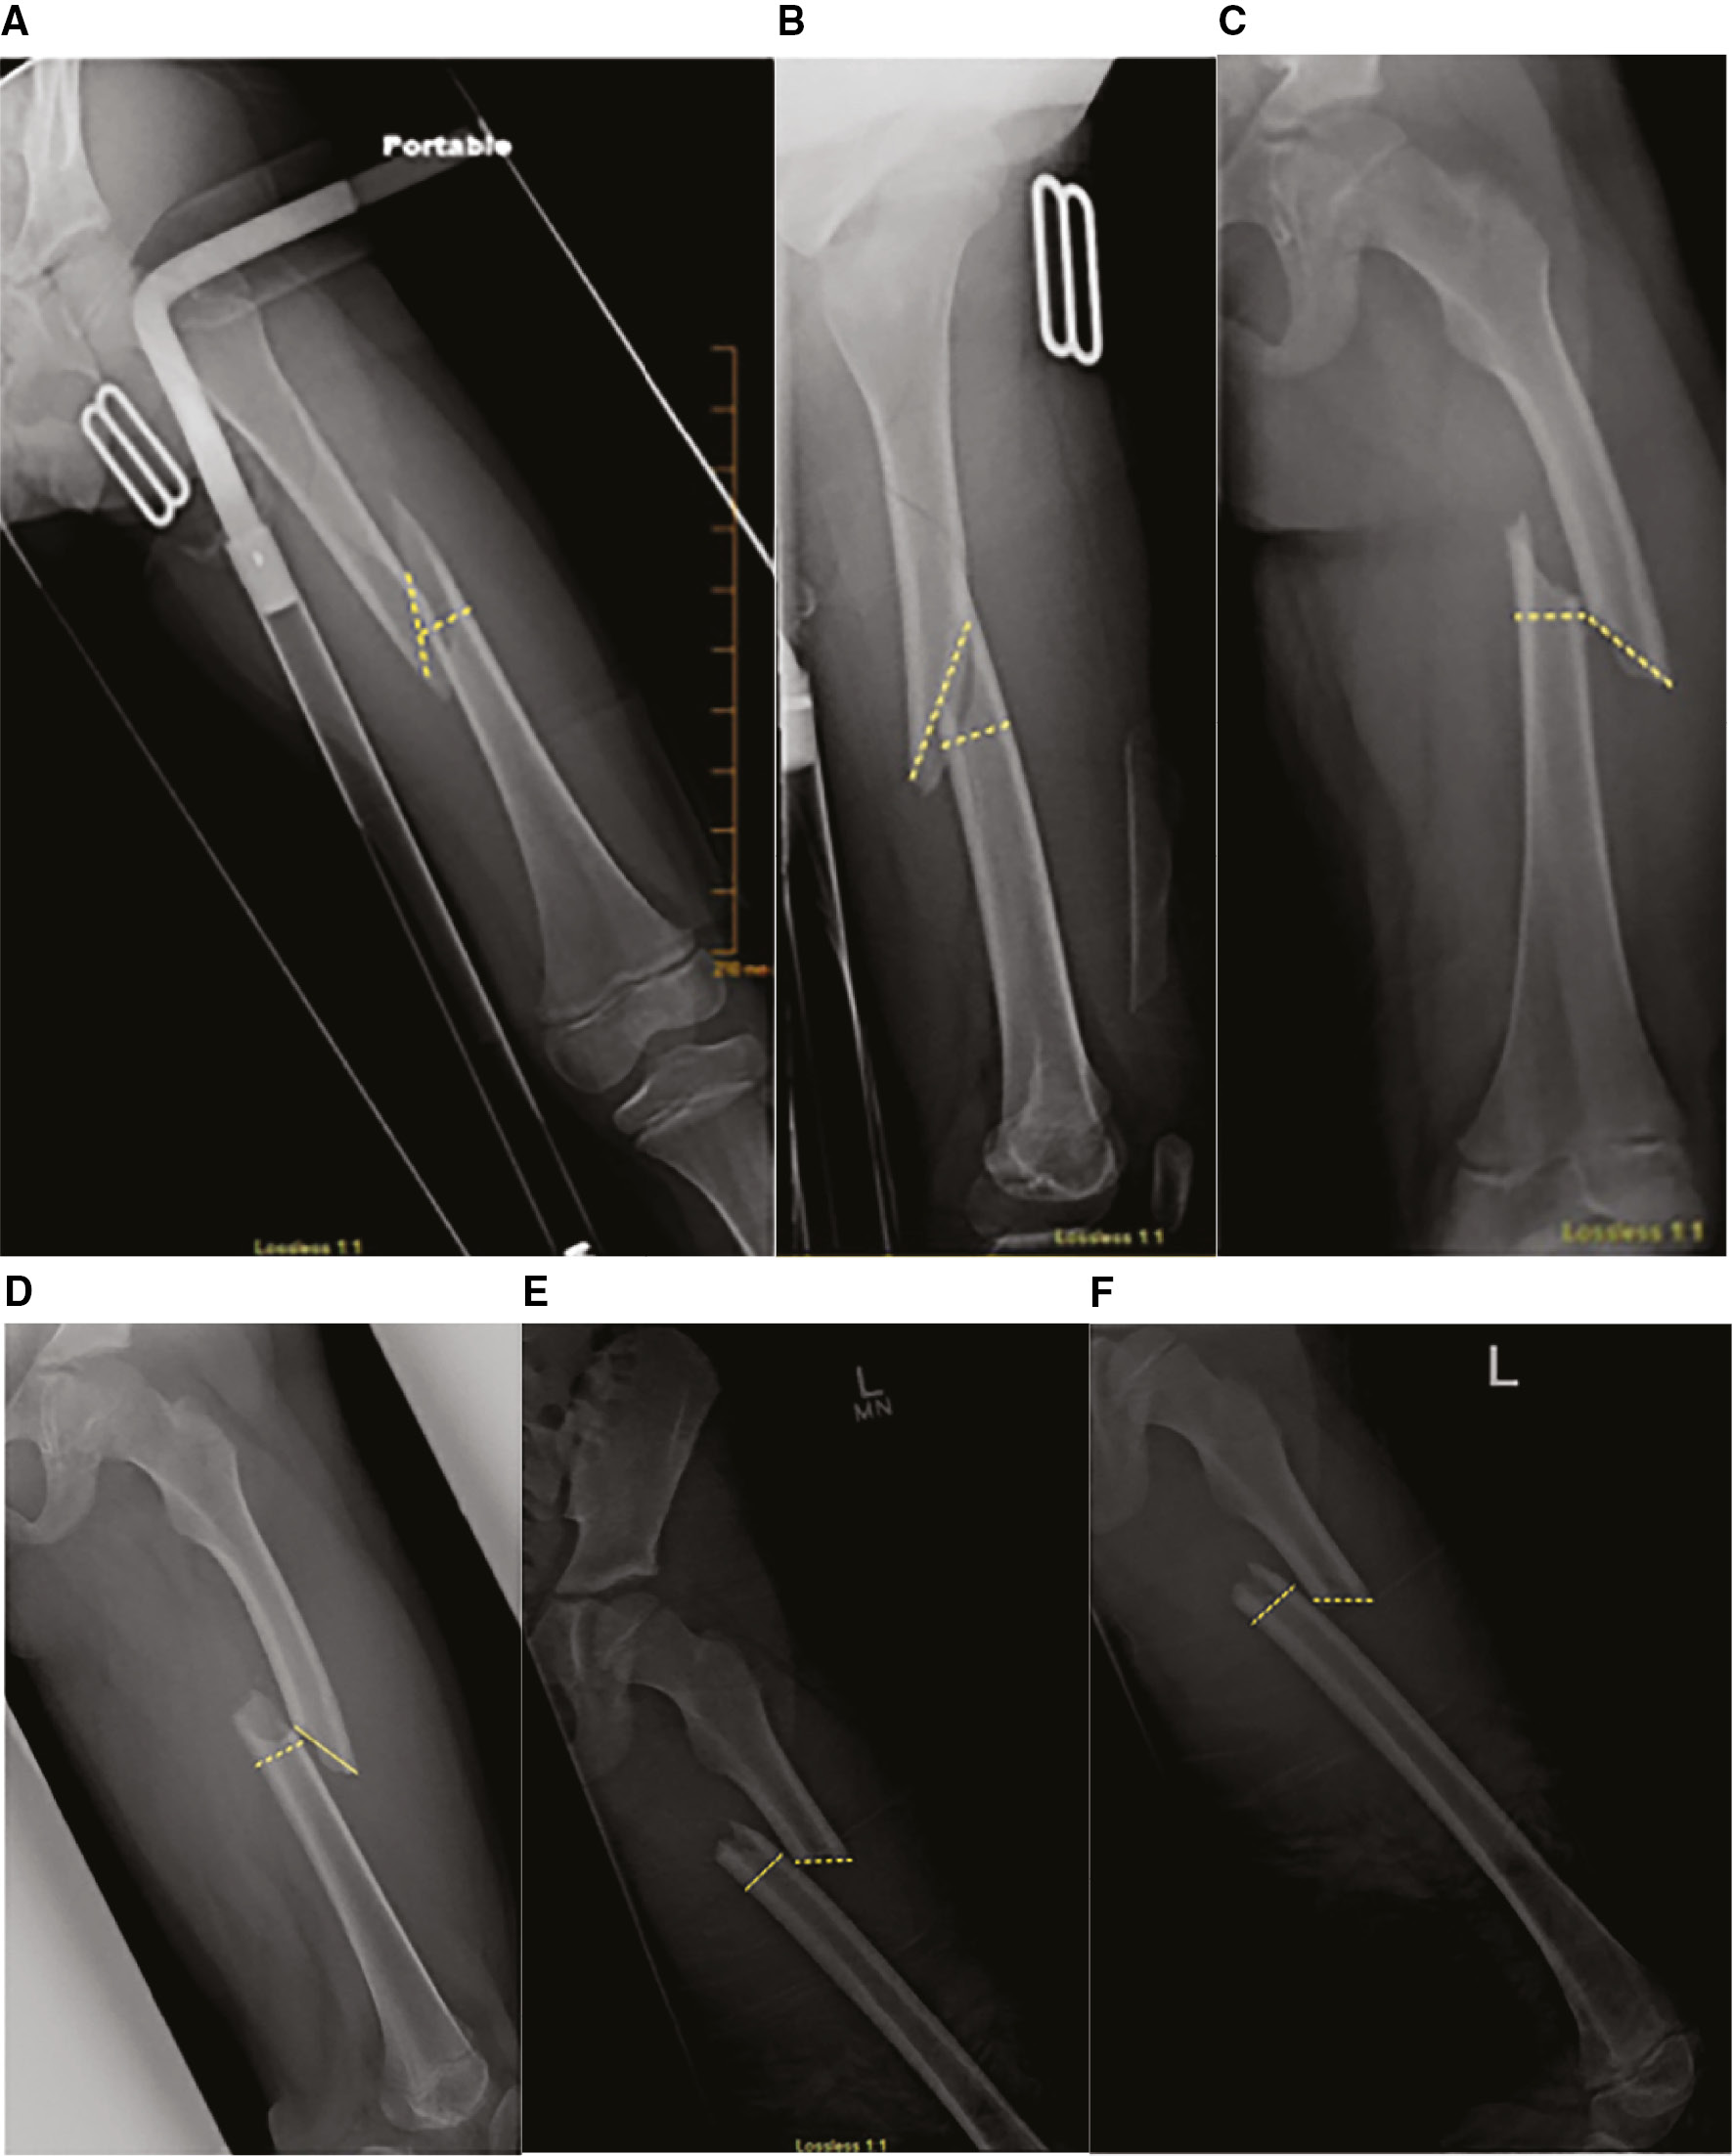

Figure 2. Prototypical morphology of spiral (A and B), oblique (C and D), and transverse fractures. Anteroposterior fracture ratios: spiral 1.86 (A), oblique 1.39 (C), and transverse 1.21 (E). Lateral fracture ratios: spiral 2.22 (B), oblique 1.86 (D), and transverse 1.21 (F).

Using transverse fracture morphology as the reference category, mean anteroposterior FR were highest for spiral fractures (1.86 ± 0.061; P < 0.0001), followed by oblique fractures (1.39 ± 0.039; P = 0.0022), and transverse fractures (1.21 ± 0.041; P < 0.0001). Using transverse fracture morphology as the reference category, mean lateral FR were highest for spiral fractures (2.22 ± 0.074; P < 0.0001), followed by oblique fractures (1.42 ± 0.047; P = 0.026), and transverse fractures (1.21 ± 0.050; P < 0.0001) (Figure 2).